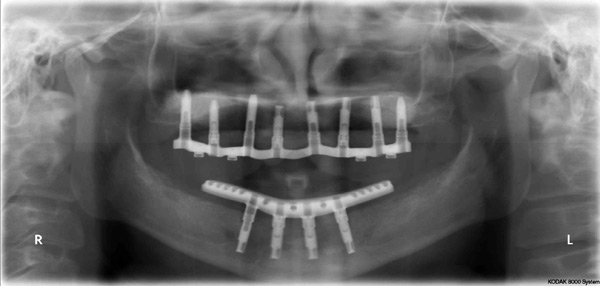

Problem: This patient presented with severe decay and a difficult occlusion/bite. He had teeth that had already been removed.

Plan: Our plan… remove the rest of the teeth and place an upper denture. Place four implants on the lower using guided surgery. Restore with a fixed/hybrid bridge.

A solution to every problem.